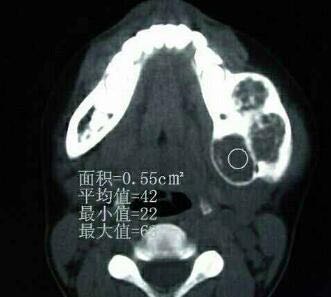

患者性别:男 患者年龄:12岁 患者病史:2月前被其哥发现左下颌肿胀,无明显不适,肿物缓慢生长。 患者症状:无明显症状

检查及结果: 颌面部左右不对称,左下颌后1|3明显膨隆,可触及鸡蛋大肿物,质硬,局部黏膜无红肿,张口度及张口型正常,CT提示:良性肿物